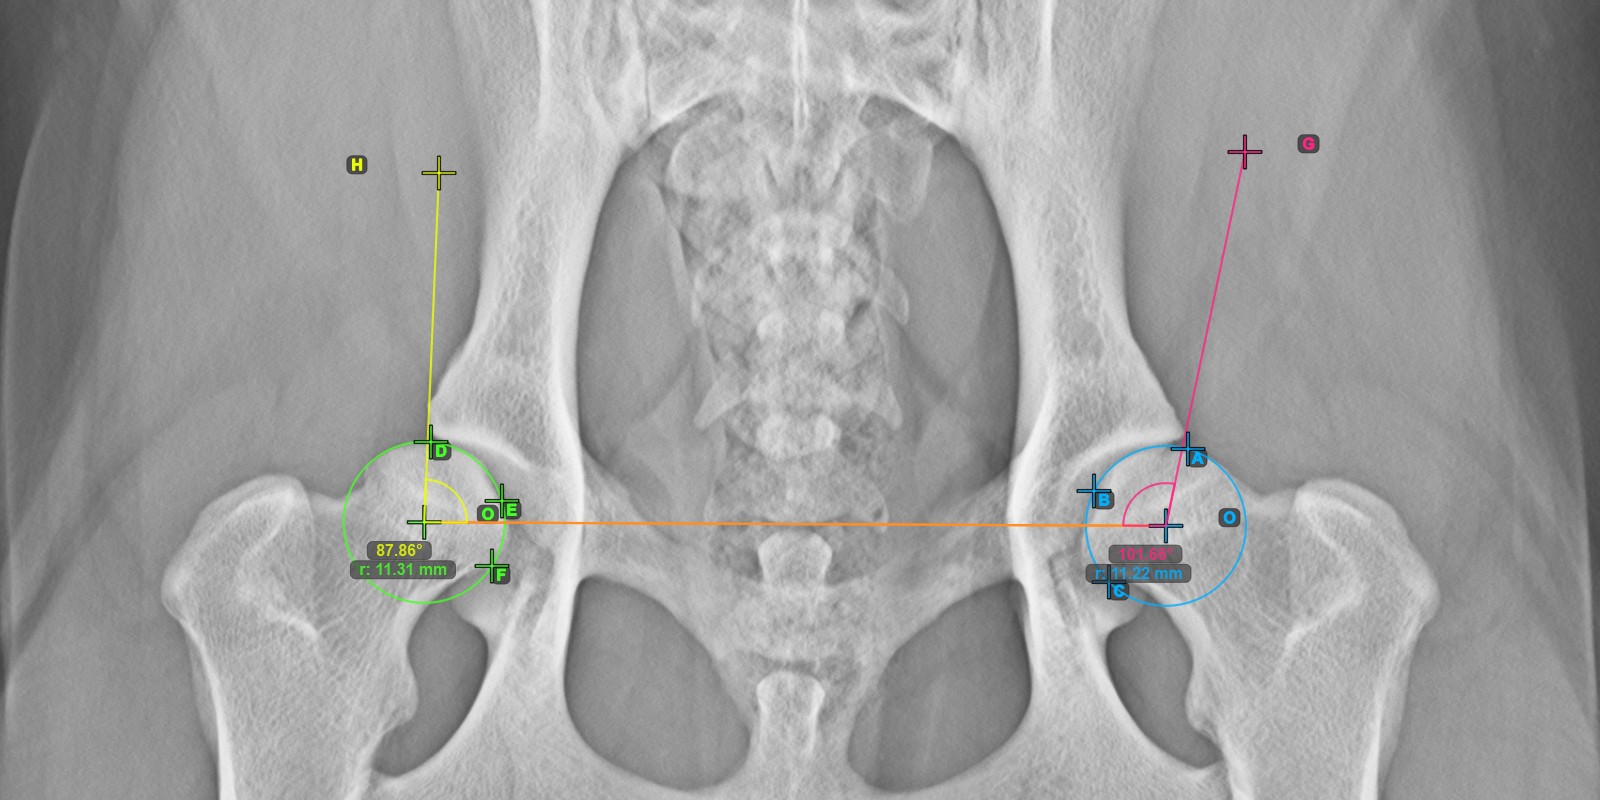

Continue by marking the three points on the articular surface of the right Caput Femoris.

Mark the three points on the articular surface of the right Caput Femoris (outside of the Fovea Capitilis). Regardless of the order, make sure to mark the most cranial point, the most caudal point and the midpoint of the femoral head. A circle will be automatically constructed based on the three placed points.

The origos of the two circles will also automatically be connected by a line, specifying the initial side of the angles yet to be constructed.

The image below depicts the typical placement of the three points on the articular surface of the right Caput Femoris.